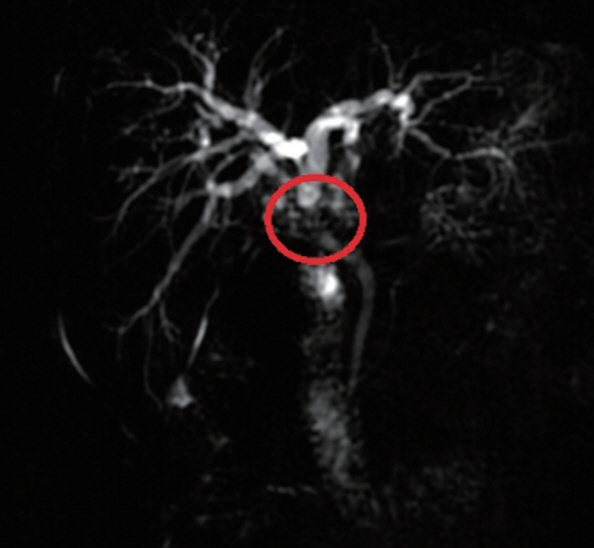

Fig. 3MRCP indicated local thickening of the upper common bile duct and luminal stenosis (red ring marker site).